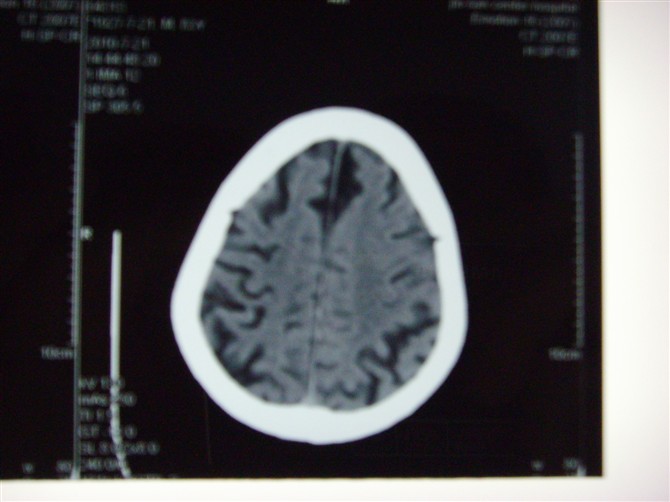

标题: CT27993:男 83岁 头晕伴双下肢无力一天 [打印本页]

标题: CT27993:男 83岁 头晕伴双下肢无力一天

脑白质疏松症,脑萎缩,复查

脑萎缩

脑萎缩。伴小脑齿状核、苍白球钙化.脑白质脱髓鞘病变

脑白质疏松症,脑萎缩!

脑萎缩,脑白质疏松症。

1)双侧小脑半球脑软化灶。2)全脑萎缩。3)脑白质病。